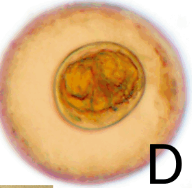

What is this the egg for?

Diphyllobothrium latum